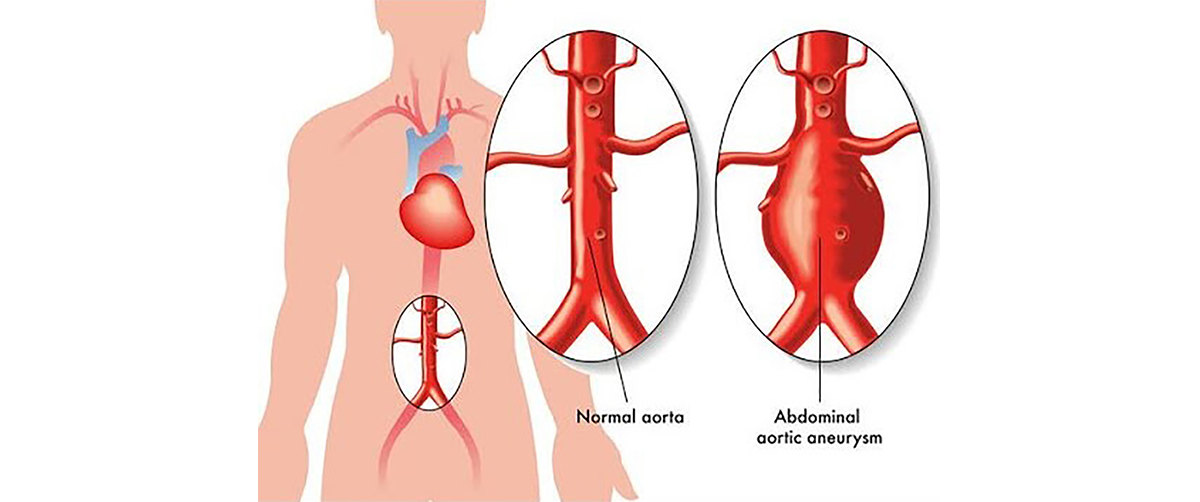

Endovascular Aortic Interventions